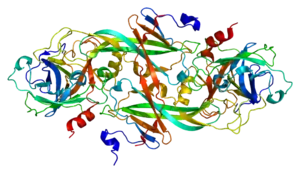

| Haemophilia C caused by deficiency in Factor XI[1] | |

Haemophilia C is caused by a deficiency of coagulation factor XI and is distinguished from haemophilia A and B by the fact it does not lead to bleeding into the joints. Furthermore, it has autosomal recessive inheritance, since the gene for factor XI is located on chromosome 4 (near the prekallikrein gene); and it is not completely recessive, individuals who are heterozygous also show increased bleeding.[1][7]